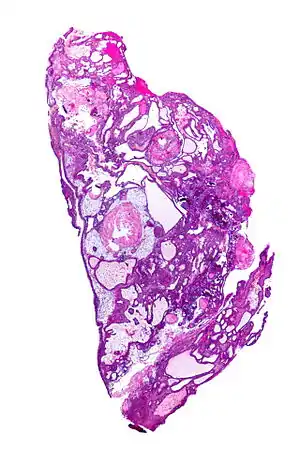

| Very low magnification micrograph of an adamantinomatous craniopharyngioma. HPS stain. | |

On macroscopic examination, craniopharyngiomas are cystic or partially cystic with solid areas. On light microscopy, the cysts are seen to be lined by stratified squamous epithelium. Keratin pearls may also be seen. The cysts are usually filled with a yellow, viscous fluid rich in cholesterol crystals. Of a long list of possible symptoms, the most common presentations include: headaches, growth failure, and bitemporal hemianopsia.

Micrograph showing the characteristic features of an adamantinomatous craniopharyngioma - cystic spaces, calcifications, and "wet" keratin, HPS stain